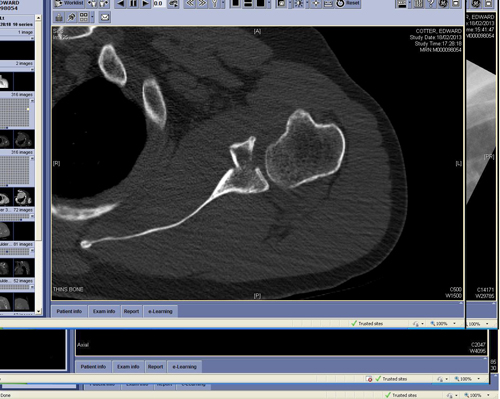

Glenoid fractures occur the margins of the shoulder joint on the scapula side and are largely due to the trauma of a shoulder dislocation. Surgery may be needed but depends more on the features of the dislocation than the fracture itself.

Other parts of the scapula can be fractured such as the scapula spine, the coracoid process or the acromion. Each is managed individually most without surgery.

The proximal humerus may fracture into multiple fragments or individual single pieces of bone associated with the attachment of the rotator cuff. Each of these fractures require careful assessment and if displaced surgical management as they are the attachment of the rotator cuff.